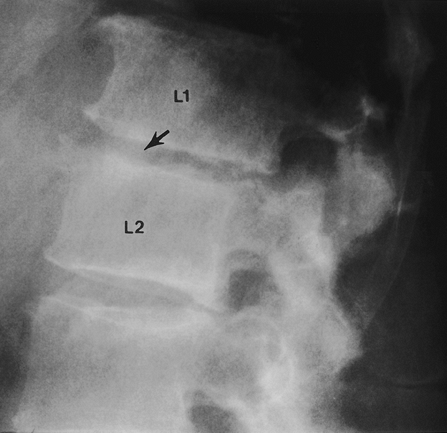

FIGURE 3-29 (A) Lateral radiograph demonstrating a Chance fracture (flexion-distraction injury). There is only mild compression (arrow) of L1. (B) AP radiograph clearly demonstrates the fracture through the posterior elements (arrows).

|